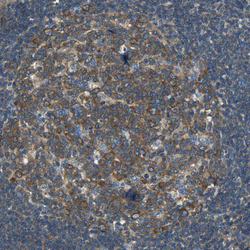

- Experimental details

- Immunohistochemical staining of human lymphoid tissues shows moderate cytoplasmic positivity in germinal center cells.

- Sample type

- HUMAN